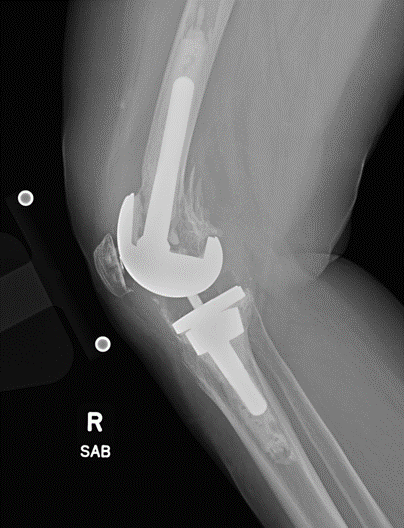

Case: 61 yo F w/ painful right revision TKA after a fall. Elevated serum Co, Cr. Not infected. Treatment of the femur? Management of well-fixed TM tibial cone?

Signficant metallosis in the joint and osteolysis about the femoral condyles. Cement-in-cement revision to DFR with retention of well-fixed TM tibial cone. Data on outcomes of retained, well-fixed cones coming in 2023!